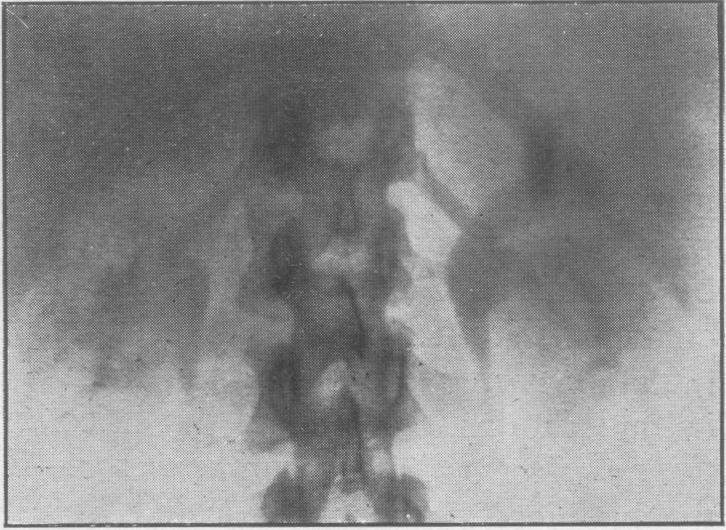

Proc R Soc Med. 1947 Mar;40(5):219-32. doi: 10.1177/003591574704000507.